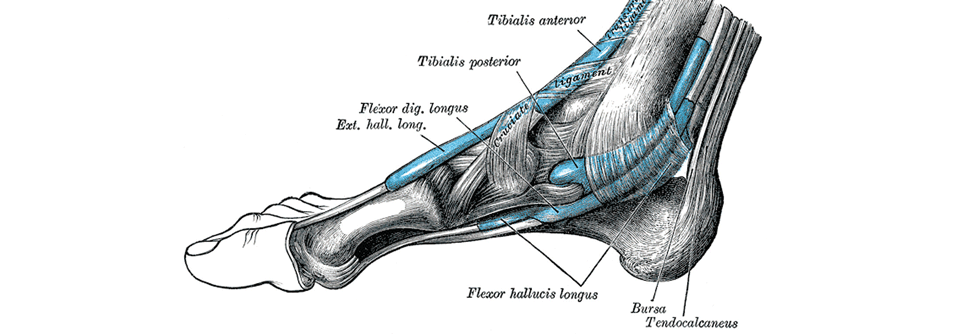

Gelenk- und Nervensonographie ergeben eine Tendovaginitis an beiden Handgelenken und rechts einen präkarpalen Nervenquerdurchschnitt von 0,14 cm², was auf ein sekundäres Karpaltunnelsyndrom hindeutet. Die MRT der rechten Hand spricht für eine Polyarthritis und eine schwere Tendovaginitis aller Flexoren und Extensoren des Handgelenks.